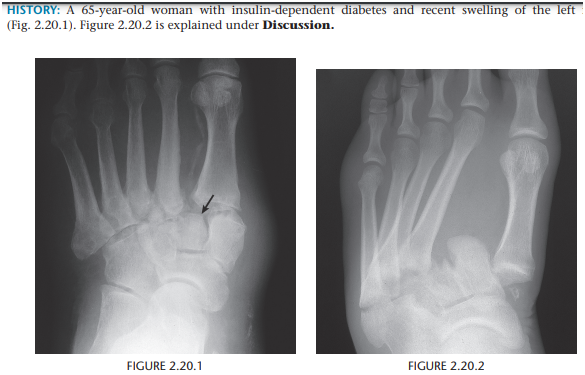

Lisfranc fracture-dislocation, homolateral

Common in diabetic neutropathy

Lack of parallel alignment of the medial aspects of the second cuneiform and second metatarsal - most important finding